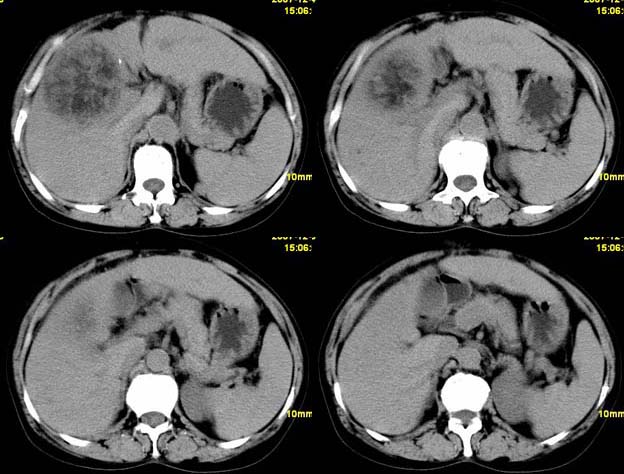

肝血管平滑肌瘤

肝血管平滑肌瘤脂肪瘤可能性大。

支持肝血管平滑肌脂肪瘤可能性大。

肝血管平滑肌脂肪瘤

考虑1肝细胞腺瘤可能性大(病灶周围有透明环影)恶变?2血管平滑肌脂肪瘤?建议穿刺病检.

肝血管平滑肌脂肪瘤可能性大,不除外包虫病

肝细胞癌偶尔也会出现脂肪变性。

肝血管平滑肌脂肪瘤可能性大;原发型肝癌待排。

支持;肝aml-------脂肪成分,中心血管征,延时强化.